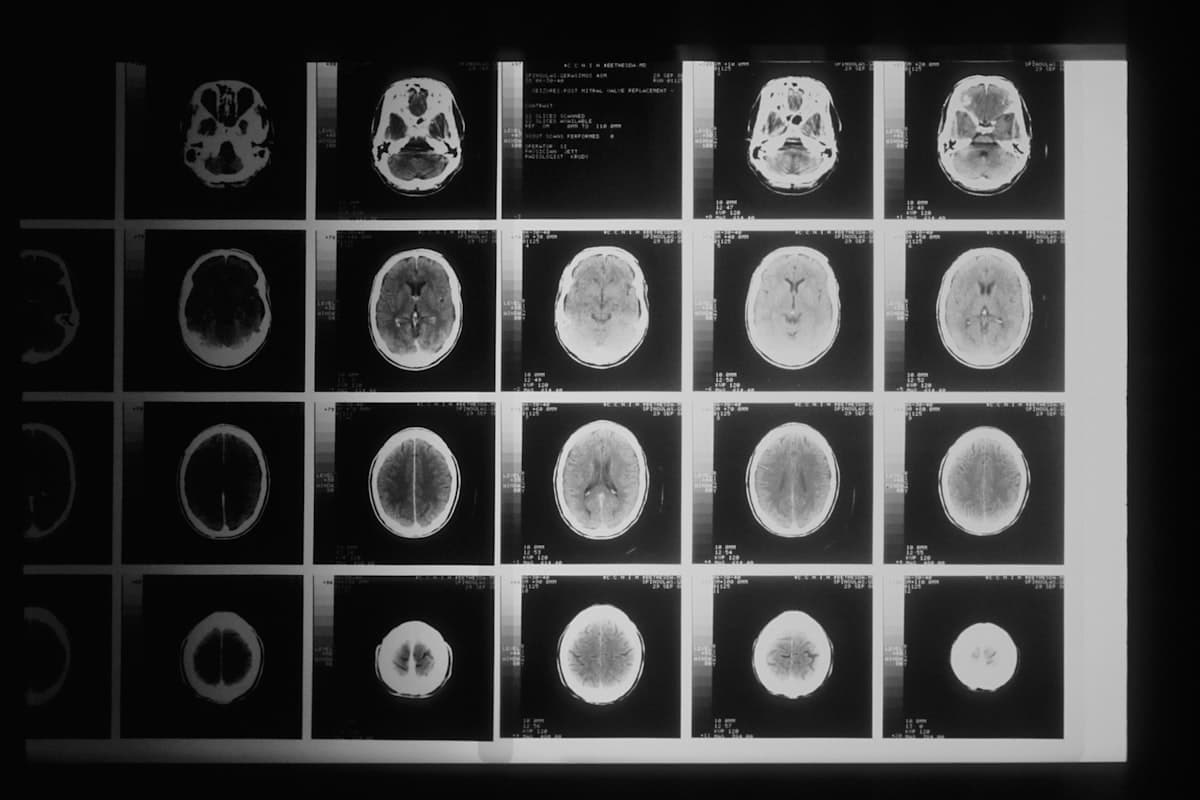

Neurosurgery

Brain, spine & peripheral nerves